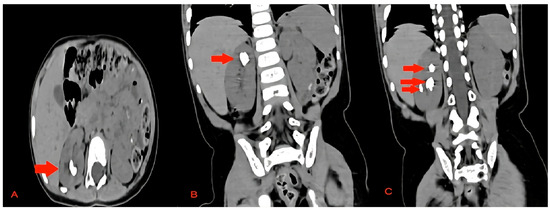

All the stones were fragmented until a size of 2 mm was reached, which was considered the threshold for spontaneous passage [9]. The whole procedure was performed under irrigation of 40 mmHg automatic pressure and the application of a manual flush if needed. Finally, a 4.7 F/14 cm JJ stent (Cook Medical, Limerick, Ireland) and an 8 F Foley urethral catheter were placed after the completion of the lithotripsy (Figure 5).

Figure 5. A fluoroscopy image after the end of the procedure showing no apparent stones.